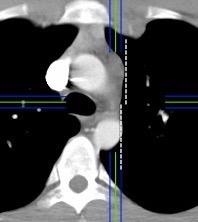

En el normal, el bronquio intermediario (BI) aparece en la proyección lateral, como una línea fina vertical que cruza el bronquio del LSI en su unión con el principal. (BPI) Engrosamiento del bronquio intermediario (BI)

97% de normales

Causas

Fallo cardiaco

Ca de pulmón

Metástasis

Linfoma

Sarcoidosis

Castleman

Schnur MJ et al.. Thickening of the Posterior Wall of the Bronchus Intermedius. Radiology. 1981

MJ et al.. Thickening of the Posterior Wall of the Bronchus Intermedius. Radiology. 1981 Ca. microcítico